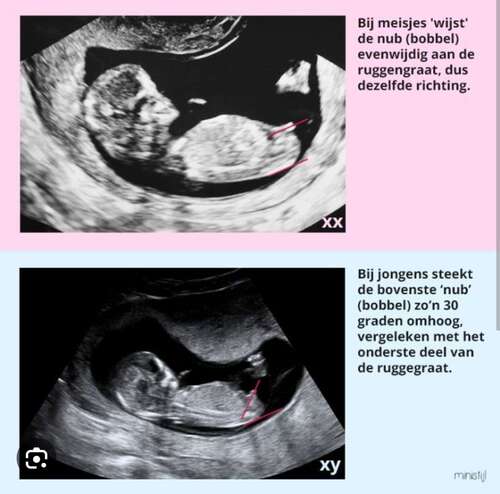

Dat het geschat wordt op basis van wat er nu gezien wordt is denk ik een logische conclusie. Echter is de termijn nog echt te vroeg, ook voor tussen de 11.3 en 12w. Ik zeg het alleen om latere mogelijke teleurstellingen te voorkomen. Alle nubs zijn op dit termijn nog een meisje.